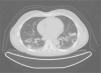

Case reportA 47-year-old male, office worker, smoker (23 pack-years) and without comorbidities, presented with subacute onset of fatigue, nonproductive cough and fever. He had been an emigrant in South America 10 years ago. Pulmonary auscultation revealed bilateral crackles in lower zones, otherwise the physical examination was unremarkable. Laboratory tests showed eosinophilia (850/μL) and mild elevation of C-reactive protein (7.9mg/dL). Bilateral opacities were observed in chest radiography and chest computed tomography, subsequently performed, showed multifocal bilateral and peripheral areas of consolidation and ground glass with perilobular pattern and halo sign (Fig. 1). Arterial blood gases were within normal range. Signs or symptoms of connective tissue disease or drug toxicity were absent and exposure history was negative. Immunological study revealed only positive antimitochondrial antibody (AMA). Due to that result and in order to exclude autoimmune liver disease, liver ultrasound was performed revealing no changes. Bronchoscopy also showed no macroscopic changes. Bronchoalveolar lavage (BAL) of right B9 segment was performed and cytological analysis revealed normal total cell count for a smoker (320×106/L), with 35% lymphocytes, 10% neutrophils, 3% eosinophils, 52% macrophages and normal CD4/CD8 ratio of 1.9. Microbiological analysis of BAL fluid was negative. Due to eosinophilia and his previous history of emigration in South America, the hypothesis of chronic pulmonary paragonimiasis was considered but research of Paragonimus westermani on BAL was negative. Transbronchial cryobiopsy of right B9 was carried out and histological examination showed poorly formed non caseous granulomas occupying terminal bronchioles and alveolar space, associated to interstitial lympho-plasmocitary infiltrate (Fig. 2). Values of pulmonary function testing were within the normal range, except DLCO (66%) that was slightly decreased. The diagnostic hypothesis of idiopathic GLD was assumed and the patient started oral prednisolone (40mg/day) therapy, presenting clinical and functional (DLCO 79%) improvement and resolution of pulmonary consolidations.